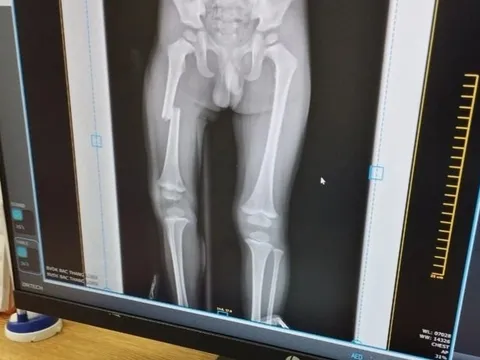

Thông tin mới nhất vụ người mẹ đạp gãy xương đùi con trai ở Bắc Giang

Công an huyện Lục Ngạn đang phối hợp với các cơ quan chức năng tiếp tục xác minh, làm rõ vụ việc để xử lý theo quy định.